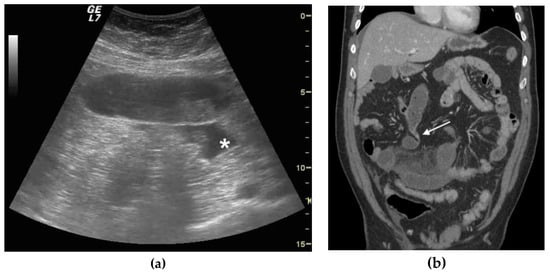

| Bowel loops diameter | Increased | Increased | Increased |

| Parietal thickness | Normal | Normal or increased | Increased |

| Valvulae conniventes | Not thickened | Not thickened | Thickened |

| Peristalsis | Present and/or hyperkinetic | Decreased | Absent |

| Free fluid | Absent | Present | Present |